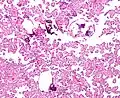

Histopathology

The tumor is neuroectodermal in origin and similar in structure to a normal choroid plexus. They may be created by epithelial cells of the choroid plexus. Papillary fronds lined by bland columnar epithelium are visible under the microscope. Normal absences include mitotic activity, nuclear pleomorphism, and necrosis.[10] Tumors have positive immunohistochemistry for cytokeratin, vimentin, podoplanin, and S-100.[11] Up to 20% of choroid plexus papilloma patients may test positive for glial fibrillary acidic protein (GFAP).[12] Studies have found that fourth ventricle cancers express more S100 than lateral ventricle tumors, and older patients (over 20 years) express more GFAP and transthyretin than younger patients.[13] Some individuals with choroid plexus papilloma have germline TP53 gene mutations, according to genetic analyses.[14] These cancers rarely exhibit nuclear p53 protein positivity. Aicardi syndrome, hypomelanosis of Ito, and 9p duplication are syndromic correlations of choroid plexus papilloma.

Plexuspapillom Detail

Plexuspapillom Overview